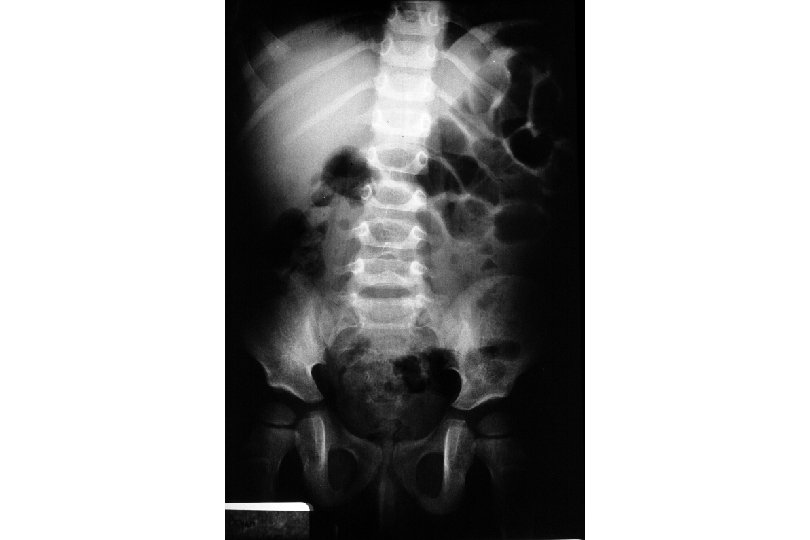

Features of the Pediatric Abdomen thinner abdominal wall with less fat and muscle decreased anterior-posterior diameter large liver and spleen extend below ribs kidney contains less perinephric fat gastric distention (with ventilation or crying) can present as a tense abdomen